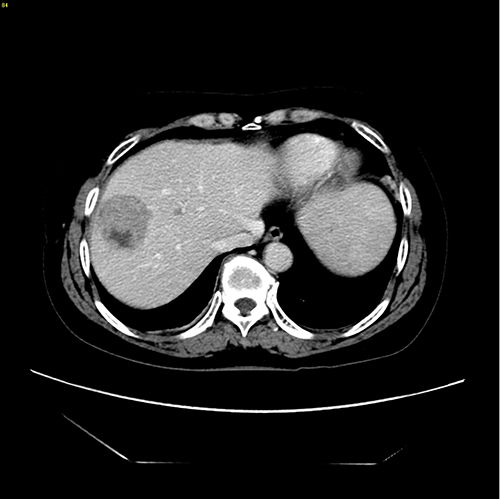

右肝肿瘤----腹腔镜右半肝切除